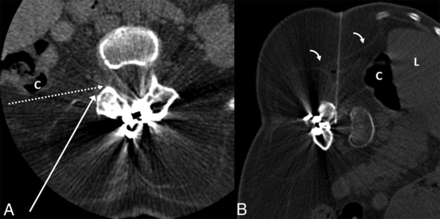

A 67-year-old woman with a history of multiple previous spinal fusion procedures presented with newly worsening low back and radicular leg pain 6 months after lumbar fusion and laminectomy. Spine MRI showed 2 paraspinous fluid collections and a large midline subcutaneous fluid collection, all of which exhibited rim enhancement (Fig 1). With clinical suspicion of abscess versus pseudomeningocele communicating with the CSF, percutaneous aspiration of the fluid collections and CT myelography were requested to determine the etiology of the pain and evaluate the provisional diagnosis of pseudomeningocele. Both procedures were scheduled on the same day at the request of the ordering surgeon, given the patient's social and transportation difficulties.

A 67-year-old woman with a history of multiple spinal fusions presented with newly worsening low back and radicular leg pain (case 1). Sagittal T2-weighted MR imaging (A) shows 2 paraspinous fluid collections (white arrows) within the deep paraspinal musculature and a midline subcutaneous fluid collection (dashed arrow) with rim enhancement on postcontrast series (not shown). B, Anteroposterior fluoroscopy image of myelography with TFLP. The needle tip is beyond the medial edge of the pedicle at the 5 o'clock position (relative to the pedicle). Note the position of the needle inferior to the expected location of the exiting nerve root and dorsal root ganglion. C, Oblique fluoroscopy image shows contrast extending into the intrathecal space after injection through the left L1–2 foramen. D, CT myelogram demonstrates the inferiorly located cystic collection filled with contrast, confirming a pseudomeningocele (arrows).

The patient was placed in a prone position under moderate sedation. The initial intent was to drain enough of the midline fluid to allow a steep oblique interlaminar approach for myelography using a combination of fluoroscopy and sonography. After 46 mL of fluid was drained, sonography showed residual fluid that, if traversed, could potentially contaminate the intrathecal compartment. Despite sedation, the patient was too agitated to safely undergo a C1–2 puncture, and rescheduling with the patient under general anesthesia was not desirable. As the back was already exposed and appropriately positioned, we elected to attempt TFLP. After re-prepping, a 5-inch 22-ga spinal needle was used to puncture the thecal sac at a 35° oblique transforaminal, infraneural approach at the L1–2 level using C-arm fluoroscopy, more oblique than usual for a transforaminal epidural injection (Fig 1). This approach was selected to minimize the risk of injury to the dorsal root ganglion, guiding the needle posterior and inferior to the known location of the ganglion seen by previous MR imaging and inferior to the conus medullaris. The patient tolerated the procedure well without any immediate complication.